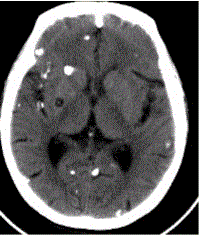

问题 患者男,45岁。头痛、癫痫10余年。查体:无发热,双侧肢体肌力正常。脑电图示双侧额颞叶棘波放电。CT表现如下图。 初步拟诊为(提示MR表现如下图:既往在内蒙古生活7年。)

选项 A.脑包虫 B.结核瘤 C.转移瘤 D.脑囊虫 E.多发性硬化 F.脑脓肿 G.腔隙性梗死

答案 D